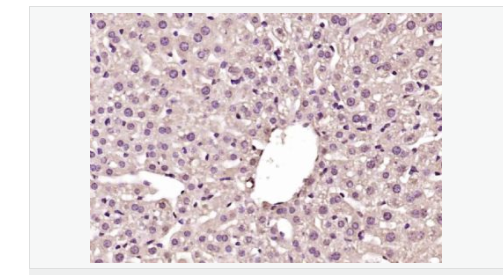

| 产品应用 | WB=1:500-2000 ELISA=1:5000-10000 IHC-P=1:100-500 IHC-F=1:100-500 IF=1:100-500 (石蜡切片需做抗原修复) not yet tested in other applications. optimal dilutions/concentrations should be determined by the end user. |